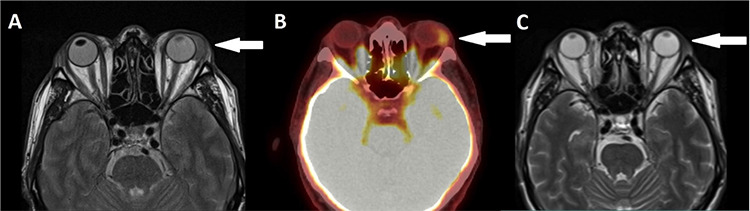

Primary Lymphoma of the Lacrimal Gland on PET/CT Imaging

PET/CT 成像显示的泪腺原发性淋巴瘤